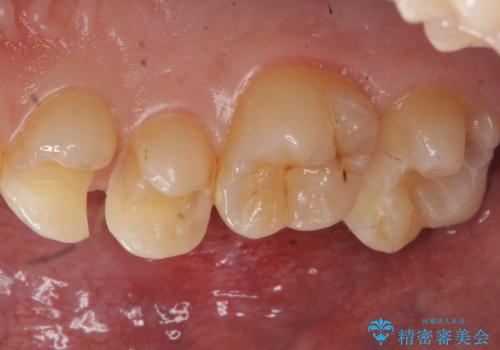

歯と歯の間の虫歯 セラミックインレーでの治療

- 検査の結果左上の歯と歯の間に虫歯が発見された患者様です。

虫歯の除去後セラミックインレーでの修復処置をしていきます。

歯と歯の間は虫歯の好発部位とされています。

適合の良いインレーでの修復をすることで再発を防止します。